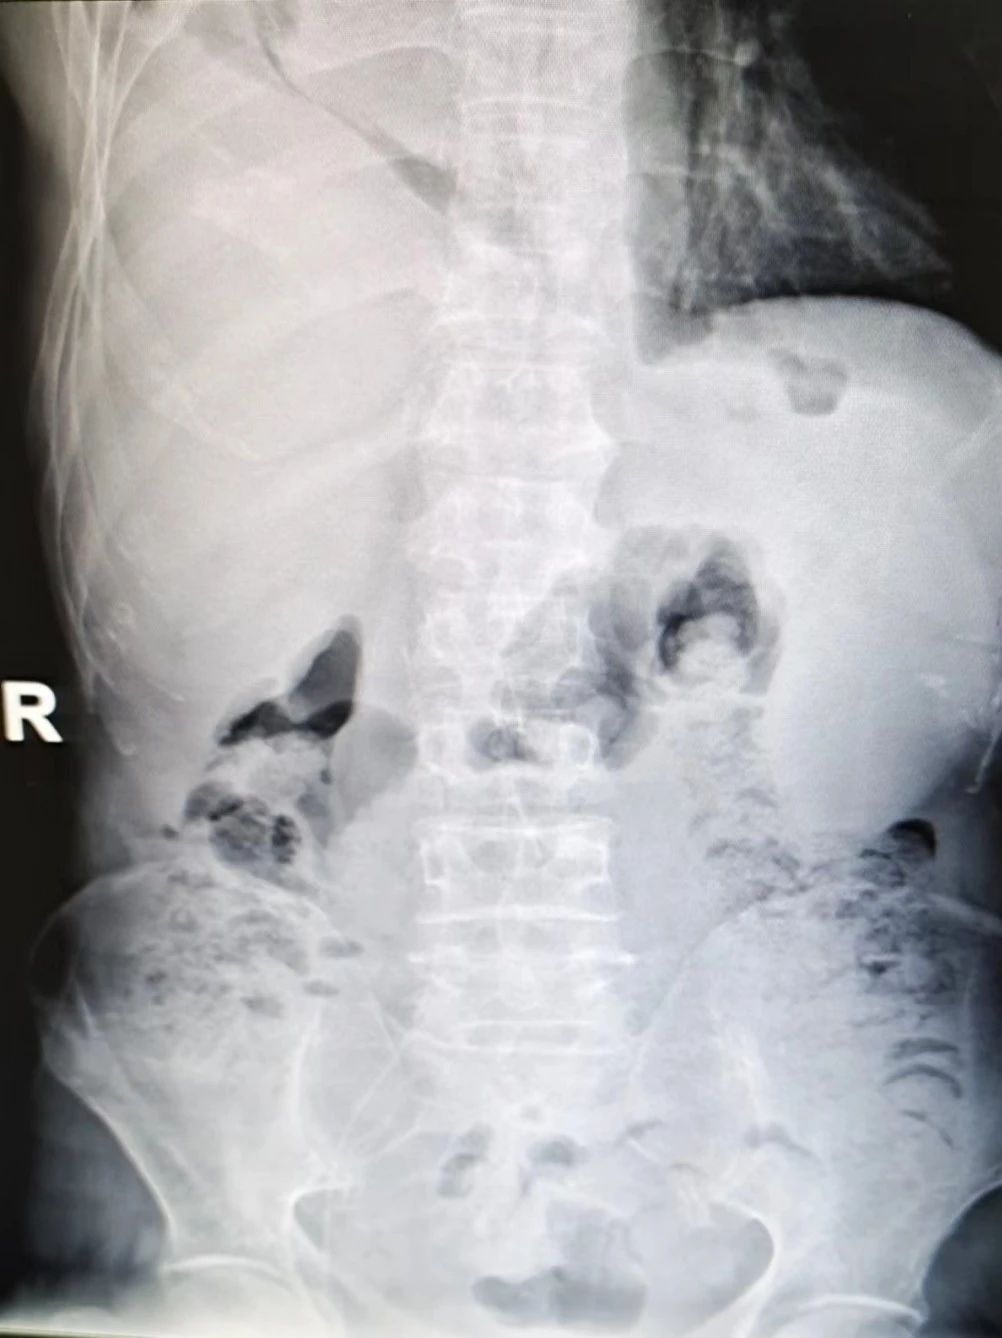

在取得患者家屬知情同意后,我院血管通路?谱o(hù)士在B超引導(dǎo)下成功為患者實(shí)施了股靜脈PICC置管術(shù),穿刺過程順利,經(jīng)X線確定PICC導(dǎo)管尖端已到達(dá)下腔靜脈。

4.導(dǎo)管尖端準(zhǔn)確置于下腔靜脈,為患者建立了一條有效的靜脈通路,使用壽命長(zhǎng)達(dá)一年,并可滿足患者化療、腸外營(yíng)養(yǎng)及支持用藥治療,也避免了化療藥物外滲引起的血管破壞。